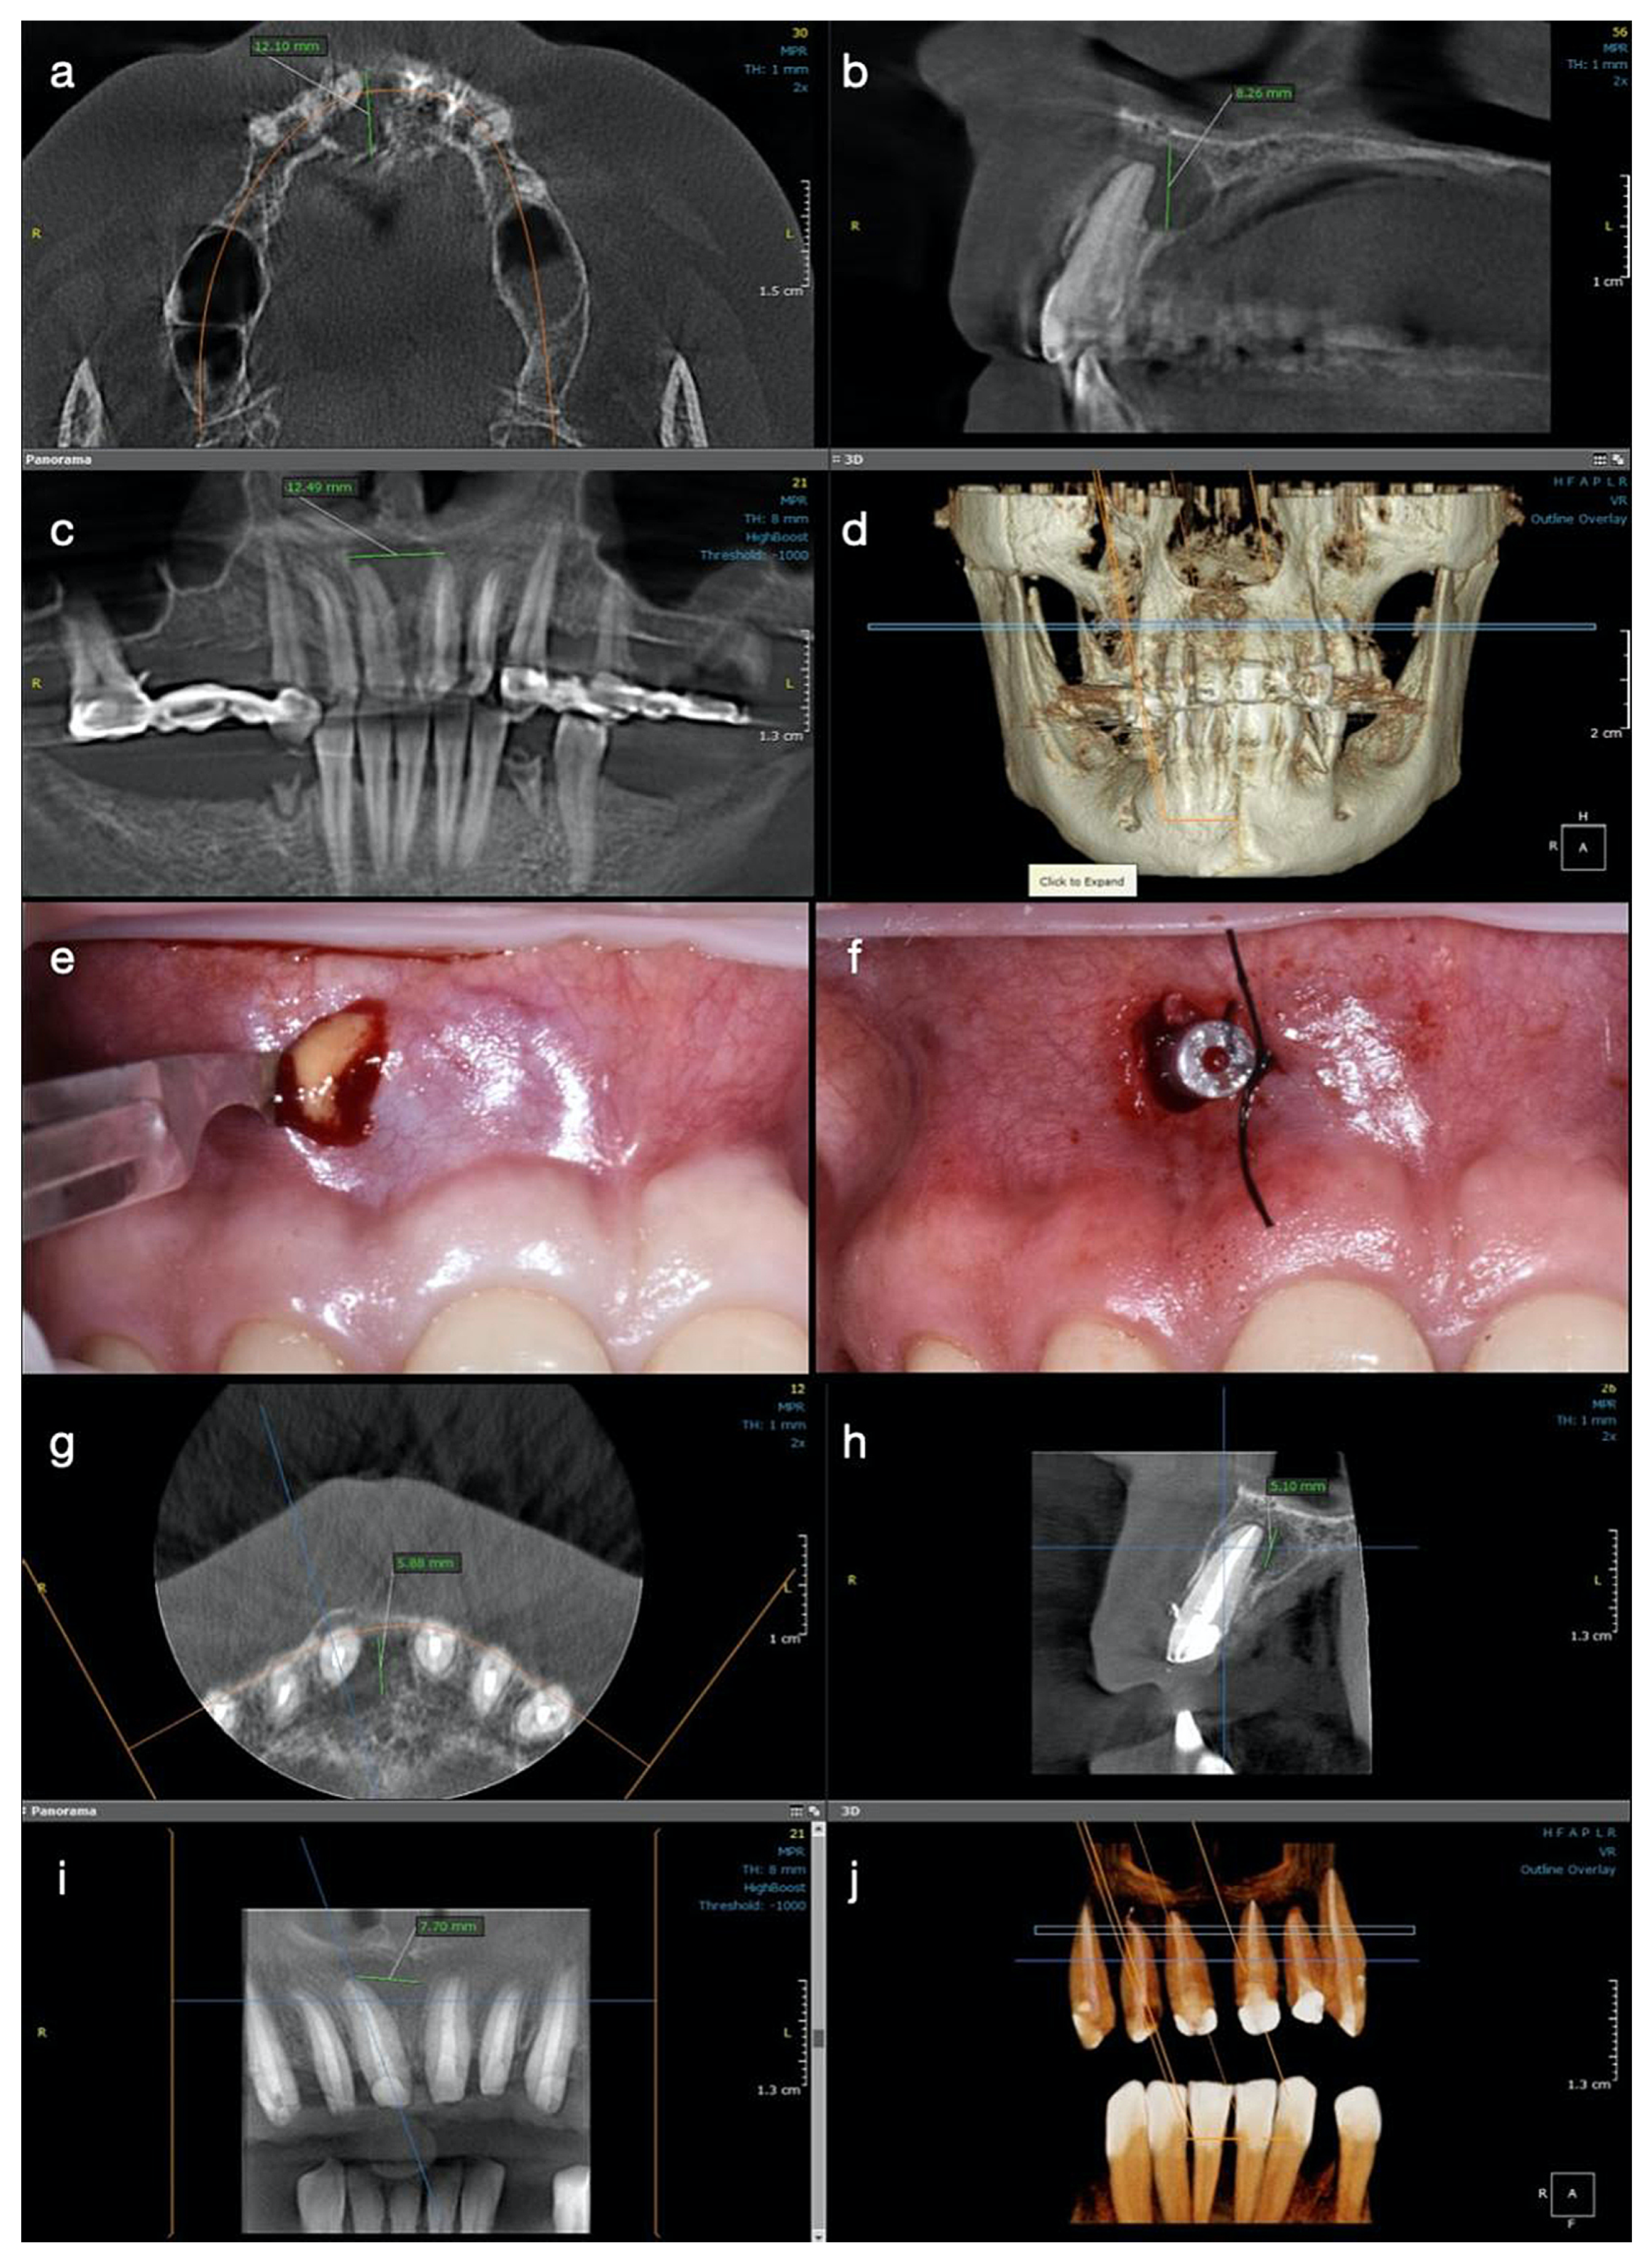

A CBCT investigation was recommended for the upper anterior teeth and performed in the dental clinic with the following parameters: 8 × 15 cm field of view, 250 µm voxel size, 90 kV, 7.1 mA, and 8.14 s emission. On the CBCT images analyzed on the 25” Dell monitor with a 1920 × 1080 pixel resolution, a large unilocular radiolucent lesion which involved the periapical region of tooth #11 was observed, extending towards the mesial region. It exceeded the middle maxillary line and was also involving the mesial part of the apical root third of tooth #21. In an upper direction, it was extending to the nasal fossa, presenting an intact nasal floor.

The size of the lesion was measured using the measurement tools of OnDemand3D (OP 3D™ Pro, KaVo Dental GmbH) and was about 15 mm in height, 13 mm in the buccolingual direction, and 13 mm in the mesiodistal. The lesion appeared well contoured by a thin radiopaque border line on all its contours, communicating with the apex of tooth 11 in its inferior part (presumptive diagnosis of pocket cyst) (Figure 2a–d). In addition, on the CBCT scan, teeth #21 and 22 appeared to be endodontically treated, with a radio-opaque obturation material present in the root canal space, 3 mm shorter from the radiographic apex for tooth #21 and 2 mm shorter for tooth #22. A small area of radiolucency of about 1 mm diameter around the apex of tooth #22 was also observed.

In order to decrease the pressure and to favour the drainage of the exudate from the periapical area of tooth #11, after local anaesthesia, a small incision in the mobile buccal mucosa was performed in the same session with a Bard-Parker surgical blade no. 15, disrupting the cystic wall. Immediately after the incision, a yellow straw-coloured fluid with a dense consistency, containing blood, pus, and cholesterol crystals, was observed draining from the lesion (Figure 2e).

Approximately 10 mL of metronidazole solution 5 mg/mL (Metronidazole B, Braun, Germany) was delivered into the lesion until a clear exudate was observed. A drainage tube was placed into the small window surgically created in the lesion’s buccal wall and was then sutured at its edges, so the drainage remained efficient (Figure 2f). The tube was removed after two days, and two weeks later the patient presented for the completion of the endodontic treatment. After the removal of the intra-canal dressing, the root canal could now be completely dried and obturated using the continuous wave of condensation technique. Post-operative instructions were given to the patient and she was scheduled for recall at three months.

At the three-month follow up, the buccal bone in the central incisor’s area became consistent at palpation, and the patient described no symptoms during this period of time or at the clinical exam. At the 6-months control, the patient was subjected to another CBCT investigation. A significant reduction in the size of the periapical lesion in a buccolingual direction, from 12 mm to 5.88 mm, and in a mesiodistal direction, from almost 13 mm to 7.70 mm, was observed with the continued increase in density of the new trabecular bone in all three plans (Figure 2g–j). The total height of the lesion was reduced from 8.26 mm to 5 mm, and the cortical buccal plate appeared significantly wider and mineralized.

Figure 2. Case 2. Radiological investigations and clinical images of tooth #11: (ad) Initial CBCT scans with the measurements of the lesion size: 12.10 mm in buccolingual direction, 8.26 mm in height, and 12.49 mm mesiodistal diameter, with the buccal cortical plate resorbed (12.10 × 8.26 × 12.49 mm); (e,f) The surgical procedure of decompression at the end of the endodontic treatment with the appearance of yellow fluid draining from the lesion, and the drainage tube fixed with sutures on the mucosa; (gj) CBCT scans and the 3D reconstruction at 6 months after the endodontic therapy, with the formation of new bone and increased reduction of the lesion size, starting from its periphery (5.88 × 5.10 × 7.70 mm).